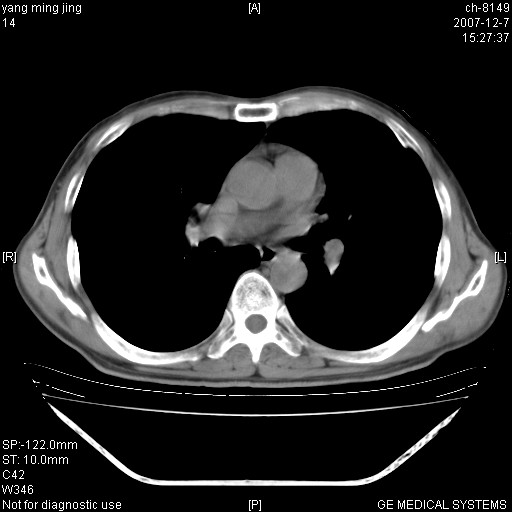

以下是引用zsl6918在2007-12-7 22:22:00的发言:[br]左肺上叶中心性肺癌并肺内及纵隔淋巴结转移,肝内转移。小细胞肺癌可能性大。

以下是引用狙击手在2007-12-8 11:03:00的发言:[br]考虑:左肺上叶中心性肺癌并肺内及纵隔淋巴结转移,肝内转移。